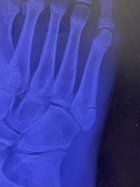

14522526:Fynluebke said:

That right there is what's known as a Jones Fracture and it fucking sucks.

What I'm guessing is - if you indeed broke it in the ski boot - you have heel lift/ lack of heel containment in your boots, and when you landed, your heel was off the sole of the boot and the inward movement of your foot in the boot caused the fracture. It could have also happened before you were skiing and you didnt even notice it until this happened.

The worst part about this type of fracture - which I believe is a zone ii jones fracture - is it takes fucking forever to heal. There's not a lot of blood supply to that section of the foot, so healing is going to take ages. You shouldn't walk on it for at least 6-7 weeks, and if after that time it hasn't begun to heal, then another 6 weeks and casting should take place...

That looks like a pretty severe break... if it's actually over about 2mm, which it could be, I would be surprised if surgery hasn't been suggested or given consideration.

Shitty.

This is possibly the point where you broke it... the right foot is pointed inwards, and the ski is leveraging your forefoot away from the counter-rotational forces of the rest of your body.

Its hard to say if this was indeed due to your ski boots fitting poorly or something else, but if there was a decent amount of space around your heel, then the rear of your foot would have had a lot of space for mobility while your forefoot was effectively immobilized by the lateral edge of your boots, while having increased leverage against it as the tip of your ski is held in place by the snow as you rotate away from it..